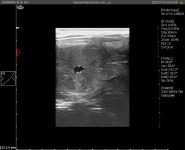

Mare Ultrasound Pregnancy Images

Equine Ultrasound Pregnancy Images

- Serial ultrasound images of early pregnancy in the mare. Discussion of variations and differences between stages seen in...